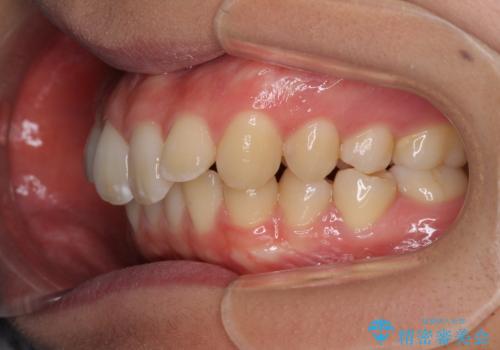

上下歯列の前後位置を見ると、上顎が全体的に前方に位置しており、上顎前歯が前方に突出しているものの、横顔の印象はそれほど口元が突出しているものではない状態でした。

口元を極端に引っ込めた印象にしないため、上顎は左右第一小臼歯2本を、下顎は左右第二小臼歯2本を抜歯し、ワイヤー装置にて矯正治療を行うこととしました。